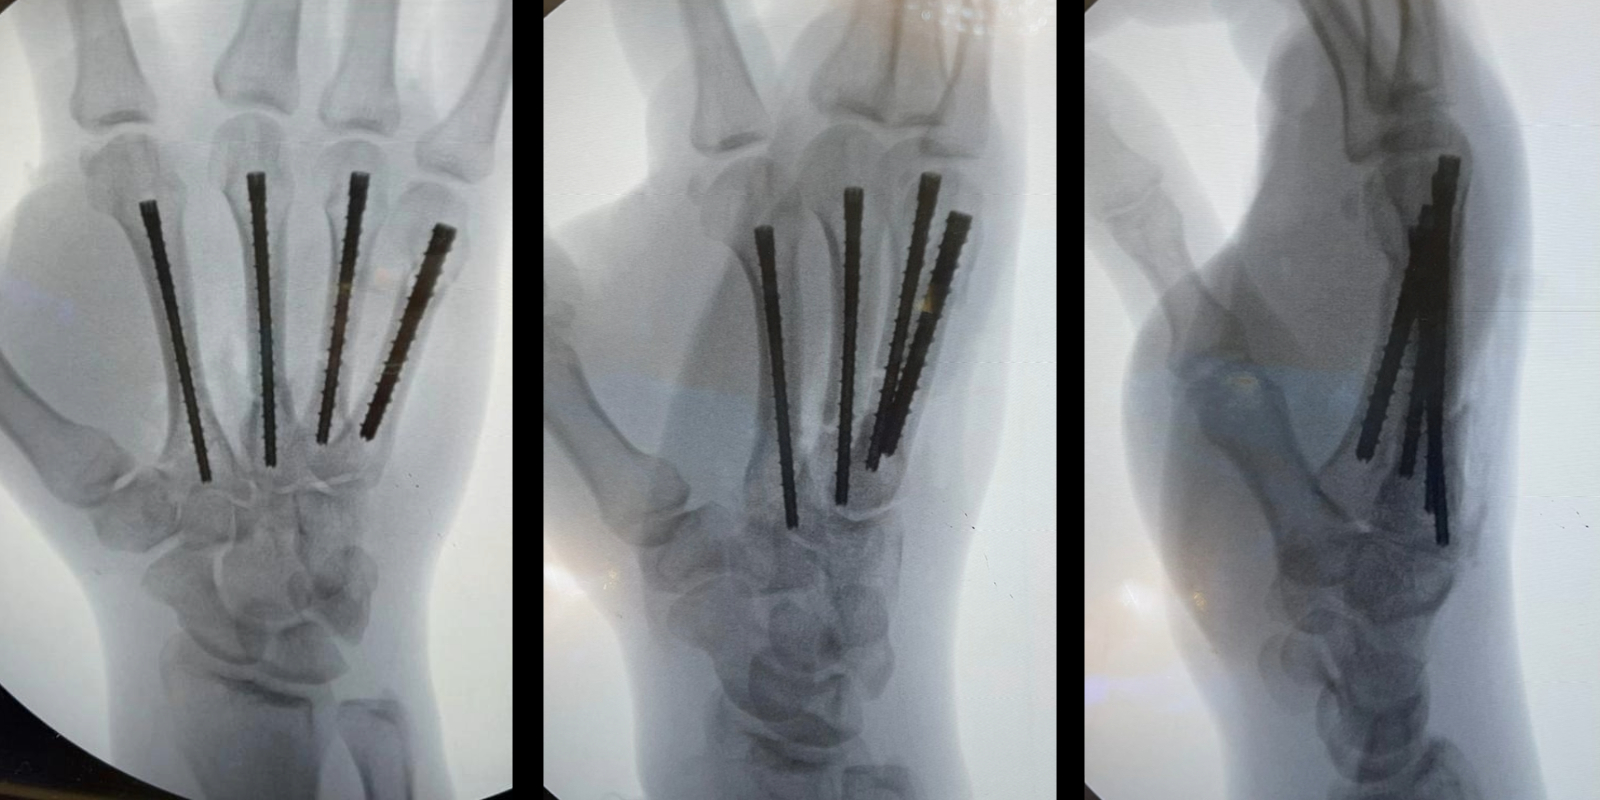

A retrograde technique was utilized for the fifth metacarpal neck and the second and third metacarpal base fractures (Video 1). An anterograde technique was used for the fourth metacarpal shaft fracture (Video 2). Following fixation, final radiographs were taken, and fluoroscopy confirmed stability with movement (Figure 2; Video 3). The hand was placed in an intrinsic plus position and a short-arm volar splint was applied. The fixation of 4 metacarpals was completed in approximately 80 minutes of tourniquet time with the splint on.

Figure 2: Postoperative radiographs of anteroposterior, oblique, and lateral views. Note the anatomic reduction with intramedullary threaded nail fixation of the second, third, fourth, and fifth metacarpals.